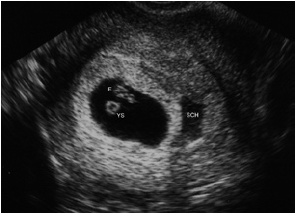

What is this?

A normal IUP with the presene of a subchorionic hemorrhage

What is a subchorionic hemorrhage?

A common source of first trimester bleeding

T or F. The presence of subchorionic hemorrhage increases the risk of SAB

T.